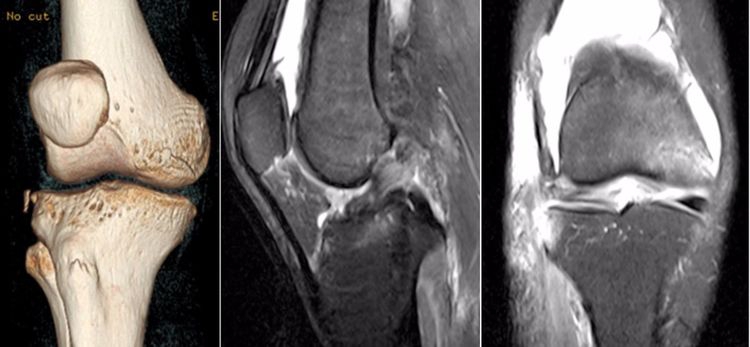

4.Segond骨折:胫骨平台前外侧撕脱骨折(胫骨平台腓骨尖上方,关节线下方的撕脱骨折),多因为下肢过度内翻加内旋暴力所致。骨折本身无特殊治疗。但其强烈提示ACL损伤(75–100%)。

ACL最常见的撕裂部位:韧带实质部>韧带股骨髁附着部>韧带胫骨附着部。由于胫骨附着部多为撕脱骨折,DR及CT均能够清晰的显示,因此很多临床医生误认为胫骨附着部的发病率更高。

4.撕脱骨折:一般为ACL胫骨附着部的撕脱,韧带完整,信号多正常。